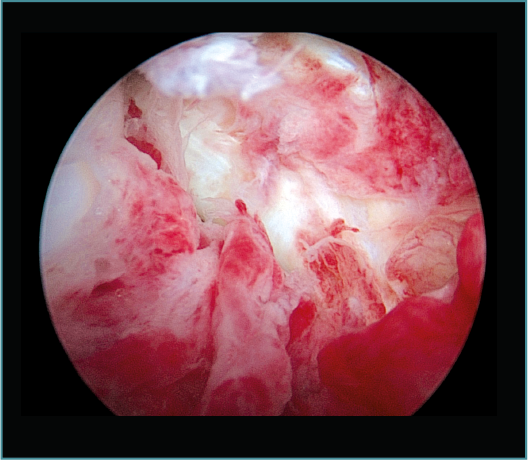

Seguidamente trabajaremos en la cámara posterior del codo, utilizando el portal transtricipital central como portal de visión y el portal posterolateral como portal de trabajo (estos portales van cambiando su función durante la cirugía y podemos añadir portales centrales y laterales más proximales, así como el portal lateral directo o soft spot)(20). No utilizamos el portal posteromedial para no poner en riesgo el nervio cubital, siguiendo las recomendaciones de Hilgersom, entre otros autores(18). En la parte posterior trabajaremos con el mismo orden: primero la resección de osteofitos en punta de olécranon, foseta olecraniana y parte lateral y medial del codo, así como extracción de cuerpos libres o tratamiento de lesiones osteocondrales en la parte posterior del cóndilo lateral del húmero (localización más frecuente), con desbridamiento del tejido inestable y/o perforaciones. Tras la parte ósea, realizaremos la capsulotomía posterior, para ganar flexión del codo (Vídeo, minutos 2:46-4:25; Figuras 9 a 14).

Figura 12. Caso 6. Visión artroscópica desde el portal anteromedial tras la resección del fragmento inestable. Se aprecia el engrosamiento y enrojecimiento de la cápsula anterior.

Figura 13. Caso 6. Visión artroscópica de la resección del fragmento osteocondral inestable del cóndilo humeral. En este caso, desde la cámara posterior del codo, con la óptica en el portal posterior central y las pinzas en el portal posterolateral.

Figura 14. Caso 6. Visión artroscópica desde el portal anteromedial tras la resección del fragmento osteocondral del cóndilo humeral; se aprecia la articulación del cóndilo con la cabeza humeral.